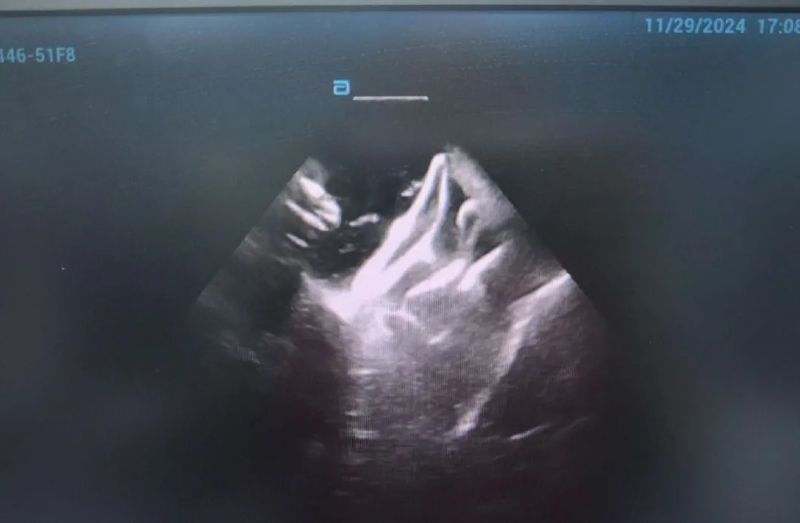

近日,延安大學咸陽醫(yī)院成功實施了咸陽地區(qū)首例脈沖場消融術、首例脈沖場消融+左心耳封堵“一站式”治療房顫手術2例手術的順利完成,標志著我院在心律失常治療技術上的又一重大突破!

此次手術患者均為持續(xù)性房顫患者,由延安大學咸陽醫(yī)院吳棟梁院長、心律失常專家劉雄濤副院長帶領介入團隊開展,安全高效、圓滿完成手術,手術過程患者全程清醒,術中自訴感覺良好,無痛苦感受。術后患者的心律恢復并維持了竇律,目前恢復情況良好,無任何并發(fā)癥出現。